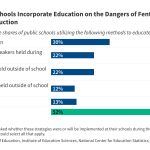

With the onset of the COVID-19 pandemic, deaths due to drug overdose among adolescents more than doubled, primarily driven by the synthetic opioid, fentanyl.